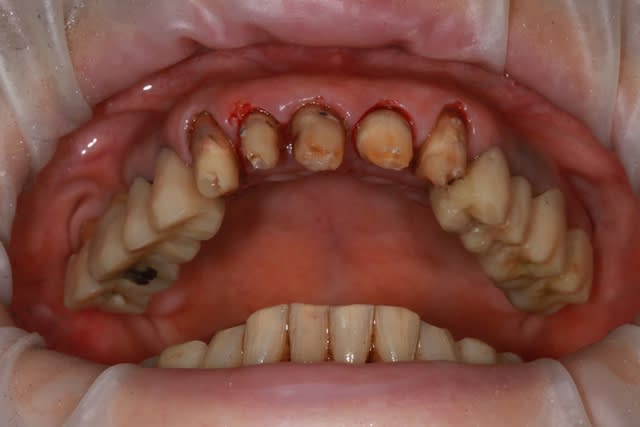

dépose des ceramo métal antérieur, ouf le précédent n'a pas mis d'IC, j'ai plus de marge de manœuvre.

Prochaine étape réalisation d'un provisoire résine "complet" pour le max.sup., mais il me faut paralléliser tous les moignons.

j'en suis à la 4eme séance détartrage surface...et ça commence à être propre et sain.